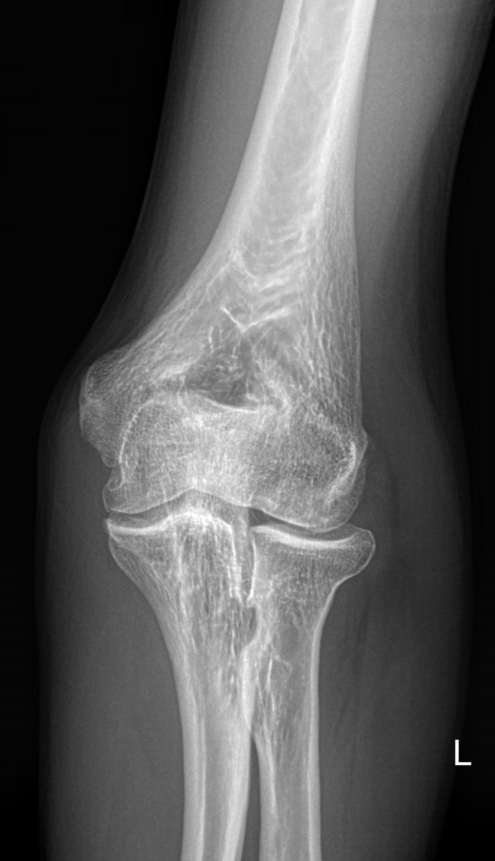

Локтевой сустав считается сложным, он состоит из 3 костей, плечевой, локтевой и лучевой, образующих, соответственно, 3 сустава. Такое строение позволяет свободно двигать рукой и поворачивать ее, обеспечивая достаточный для человека объем движений. Патологии сустава серьезно ухудшают двигательную активность и вызывают болезненные ощущения.

Что покажет рентген локтевого сустава

• Отек мягких тканей;

• Конгруэнтность и состояние суставных поверхностей, например, наличие эрозии и уплотнение суставных поверхностей, а также костные разрастания

• Состояние суставной щели ― сужение, выпот, обызвествление капсулы;

• Структура костной ткани ― типичная, деструкция или участки повышенной плотности и вздутия, остеопения, иные патологии;

• Травмы ― переломы;